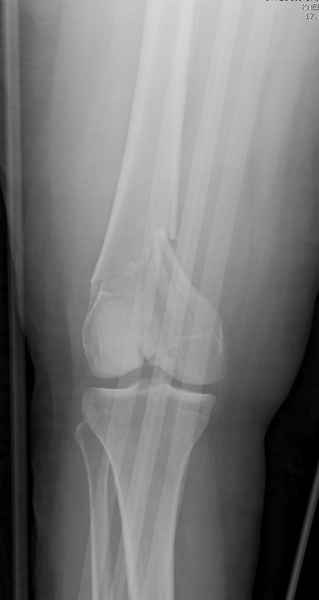

Привет из Нижнего Новгорода! К нам поступил пациент 25 лет с закрытыми переломами обеих бедренных костей, прошел месяц после травмы. Слева - внутрисуставной перелом, поэтому выбор здесь очевиден, открытая репозиция, стабильная фиксация, скорее всего LCP DF, а справа - мнения учёных, как говорится, разошлись. Лично я, как лечащий врач, за закрытый интрамедуллярный остеосинтез DFN. Со мной согласна половина коллектива, другая - за интрамедуллярный остеосинтез (DFN,UFN) но с открытой реопозицией, поскольку при закрытой методике все осколки останутся где-то сбоку, получится дефект и вдруг не срастется!Философский вопрос: что лучше - красивая рентгенограмма или сохранение кровоснабжения? Очень важно мнение коллег! Смирнов Алексей

При наличии различных имплантов, любые варианты: слева (полу) открытым - мининвазивным, а справа закрытым интрамедуллярным методом, его считаем более чем приемлемым для фиксации данных переломов.

Проксимальная и дистальная блокировка, независимо от техники введения штифта, ретроградно или антеградно, гарантирует сращение сегментарных переломов бедра без укорочения. Штифты диаметром 12 мм с блокировкой сверху и вниз двумя шурупами выдерживают вес 75 кг больного, что позволяет раннюю профилактику контрактур.

Погоня за "красивой рентгенограммой" не всегда оправдана для фиксации кости, где имеется массивное мягкотканое покрытие. Если так уж хочется исправить положение кости, то при наличии ЭОП, большие костные фрагменты могут быть развернуты или приближены к основному фрагменту методом применения Joystick.